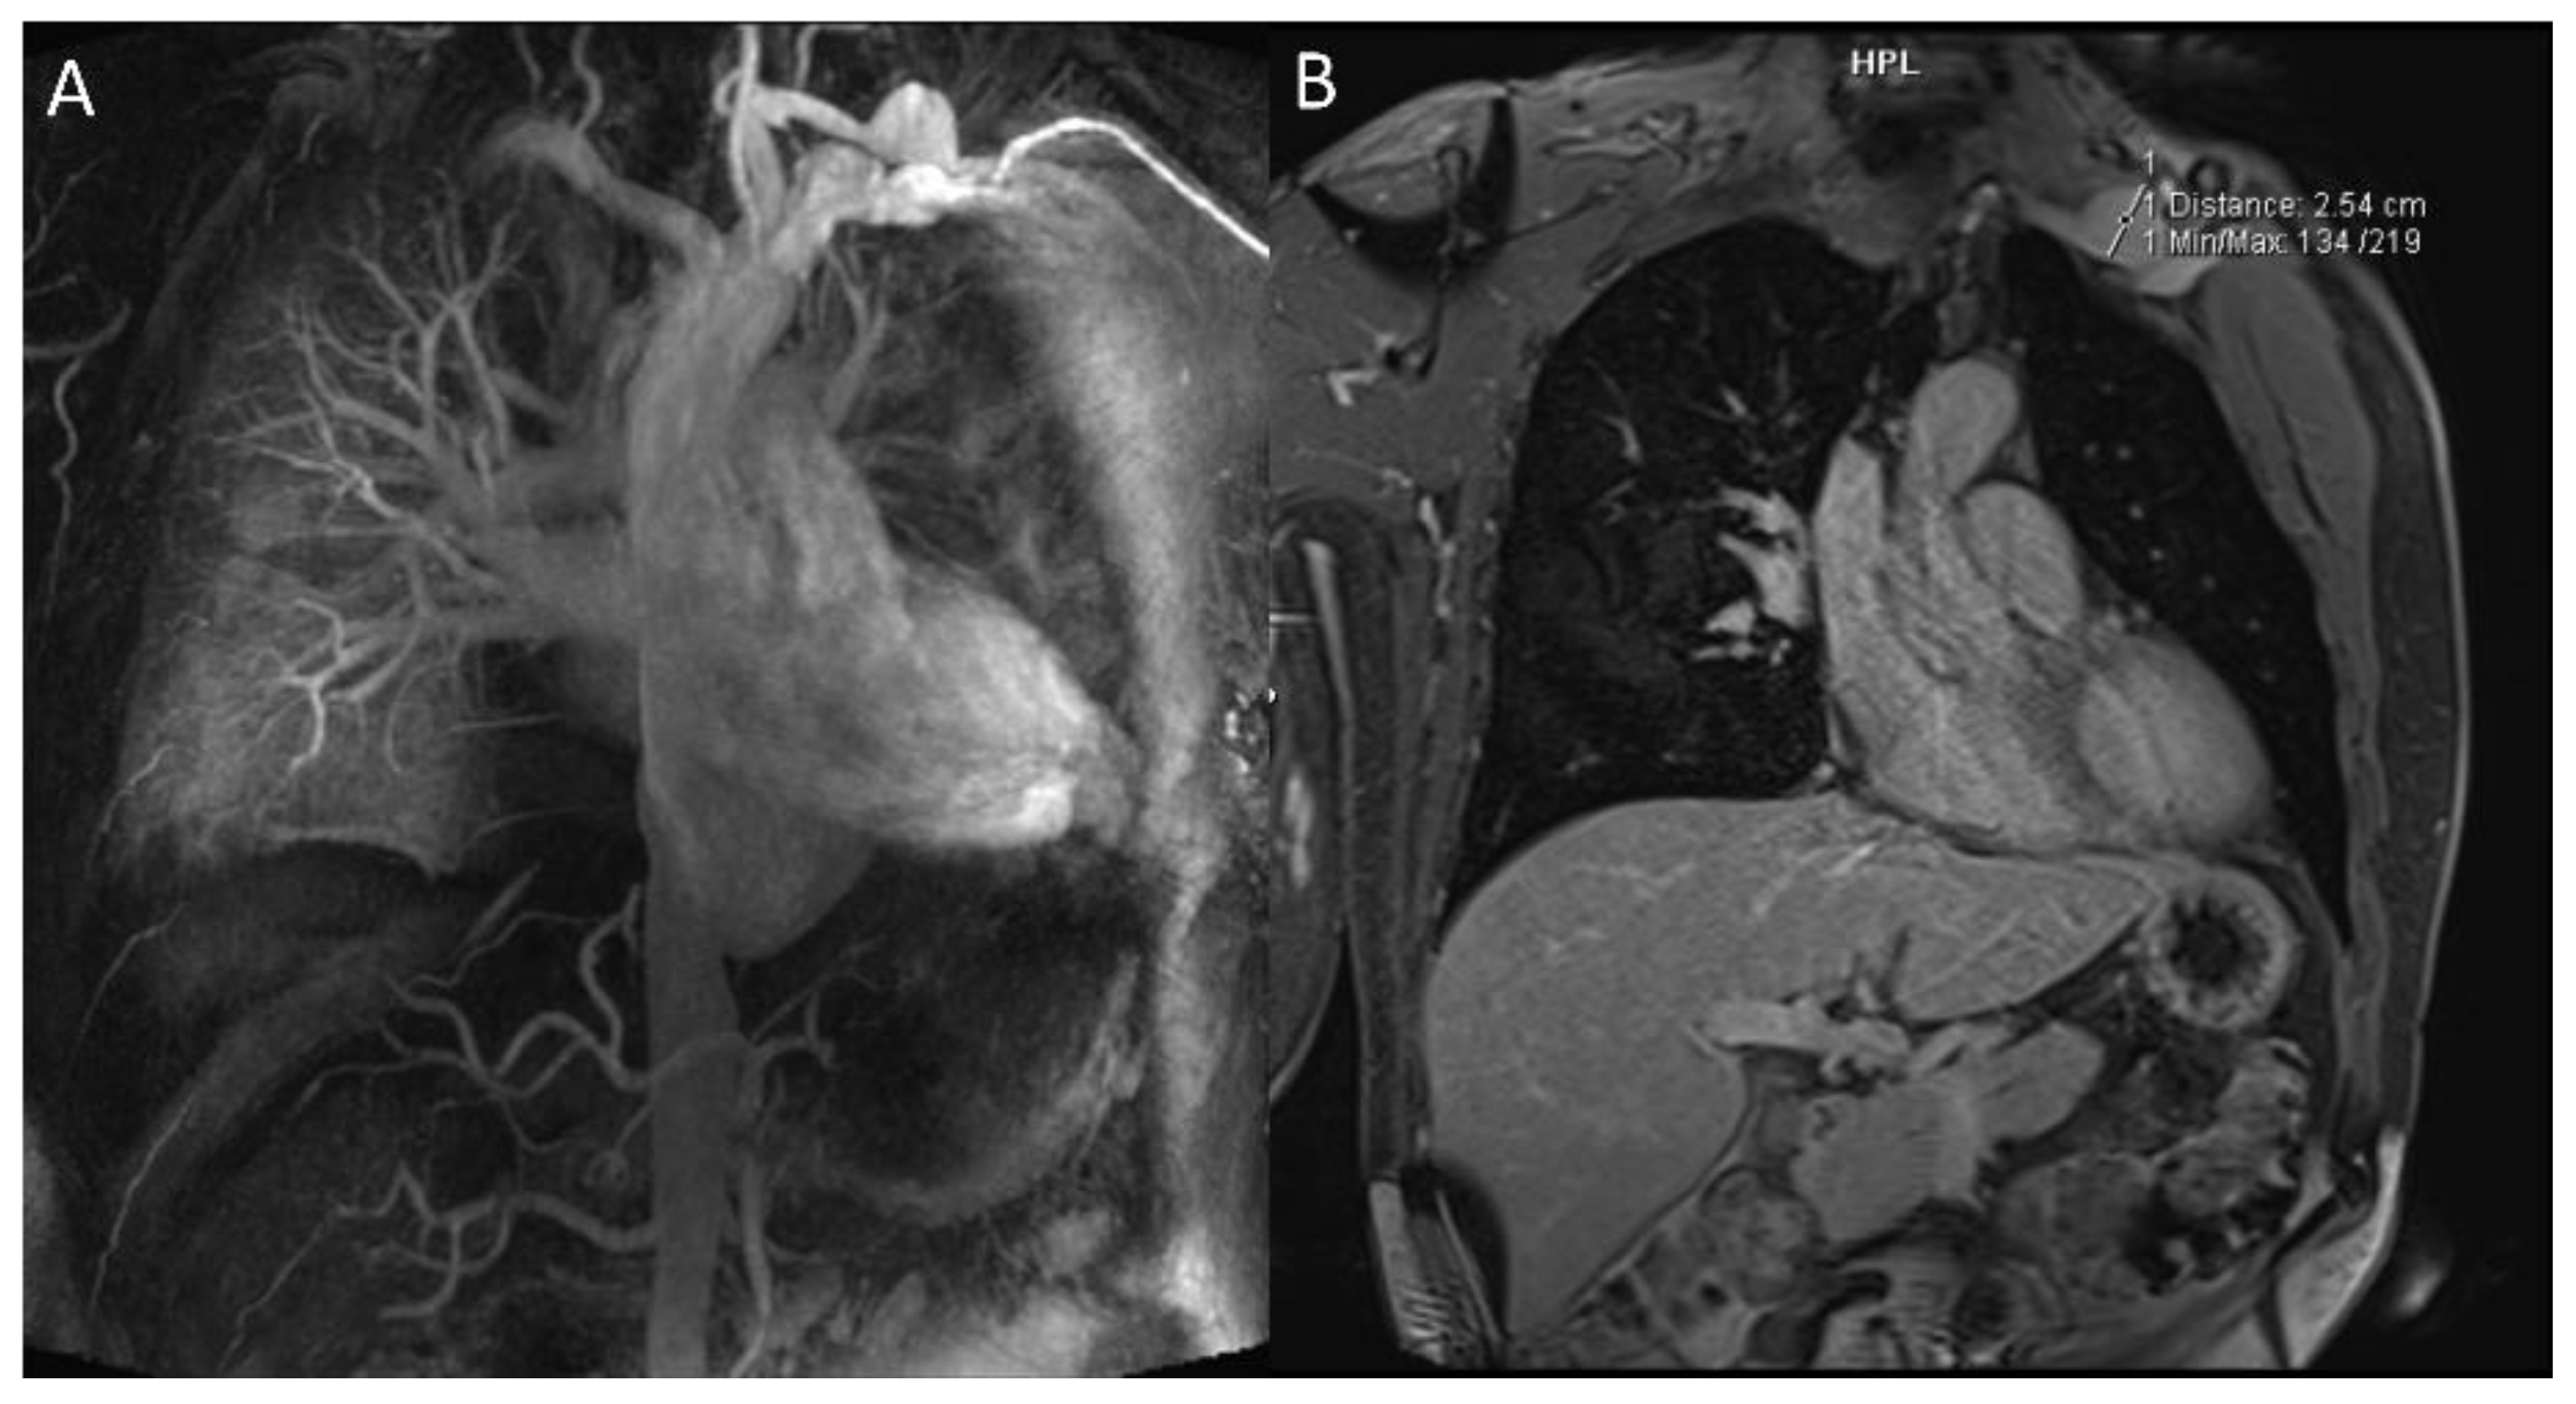

2.1.2. Pulmonary Arterial Manifestations

- Akpolat, T.; Danaci, M.; Belet, Ü.; Erkan, M.L.; Akar, H. MR Imaging and MR Angiography in Vascular Behçet’s Disease. Magn. Reson. Imaging 2000, 18, 1089–1096. [Google Scholar] [CrossRef]